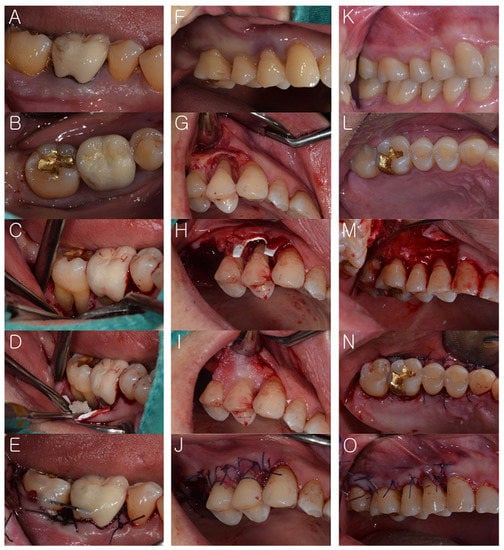

One periodontist (JTL) performed all surgical procedures. The patients received oral hygiene instructions before periodontal surgery. Under local anesthesia using 2% lidocaine (1:100,000 epinephrine, Huons Co., Ltd., Sungnam, Korea), the surgical sites were treated. In the GTR group, a full thickness flap was performed. The exposed defects were carefully scaled and root planed using a combination of mechanical and hand instruments. DFDBA (Human Cortical Powder, Demineralised, DIZG, Berlin, Germany) was applied to the defect area. A cross-linked-collagen membrane (OssGuide, Hyundai bioland Co., Ltd., Cheongju, Korea) composed of porcine pericardium-derived type I collagen was used. It was trimmed to the local anatomy and then positioned on the graft material. Then, the flap was replaced and sutured with resorbable sutures (4-0 Vicryl, Ethicon, Somerville, NJ, USA). All patients were prescribed amoxycillin and clavulanic acid 375 mg (Augmentin, Ilsung Pharma Co., Seoul, Korea), naproxen sodium (Anaprox, Jongeun Dang Pharmceutical, Co., Seoul, Korea), and almagate (Almagel, Yuhan Pharma Co., Seoul, Korea) 3 times daily for 1 week unless an allergy to penicillin was present. All patients were instructed to rinse for 30 seconds twice daily with 0.12% chlorhexidine gluconate (Hexamedin, Bukwang Pharmaceutical, Ansan, Korea) for 1 week. Sutures were removed 2 weeks post-surgery. In the Flap group, full thickness flap, scaling, and root planing were performed. Irregular bony protrusion was removed with rotary or hand instruments. After debridement, the flap was repositioned and sutured. The same medicines were prescribed as in the GTR group (Figure 2).

Figure 2.

(Case 1: A–E and Case 2: F–J): Guided tissue regeneration (GTR); (A–B,F) before treatment, (C,G) full thickness flaps were performed; then, the exposed defects were carefully scaled and root planed, (D,H–I) demineralized freeze-dried bone (DFDBA) and collagen membrane were applied to the defect area, (E,J) suture and resin wire splint were performed. (Case 1: K–O): Open flap surgery (Flap); (K,L) before treatment, (M) full thickness flap and debridement were also performed, (N,O) suture was performed.